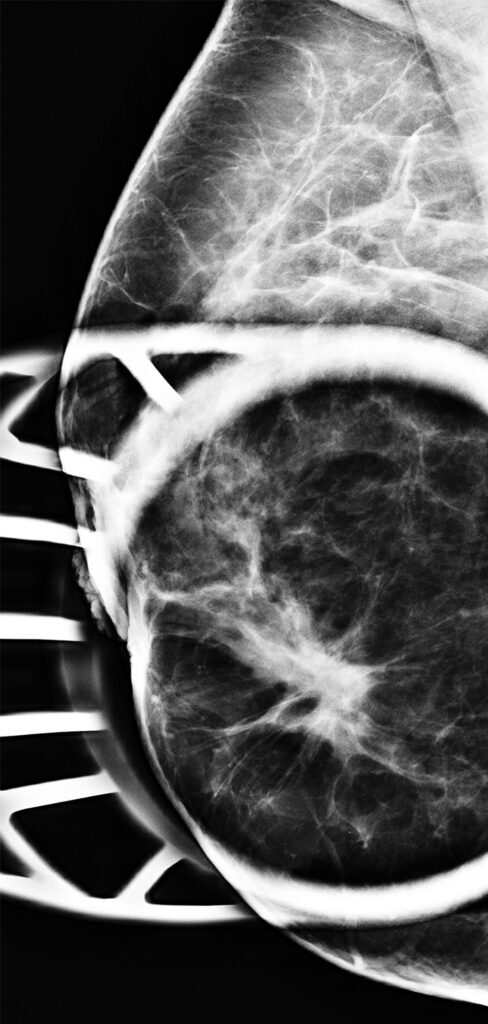

BI-RADS 5: More than Cancer

El artículo resalta que la evaluación por imágenes de la mama se hace por medio los parámetros descritos en el BI-RADS del Colegio Americano de Radiología, para que todo el personal que maneja estos estudios pueda manejar el mismo léxico.